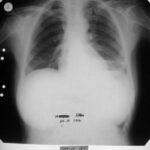

Mayıs 1993 (6. Ay)

Şikâyeti kalmamıştı ve immünomodülatör tedaviyi bırakması önerildi.

✅ Tam İyileşme

1998 (6 yıl sonra): Takipte remisyon devam etti

2002 (10 yıl sonra): Takipte remisyon devam etti

Hasta normal yaşamına tamamen döndü ve hastalık belirtisi göstermedi.